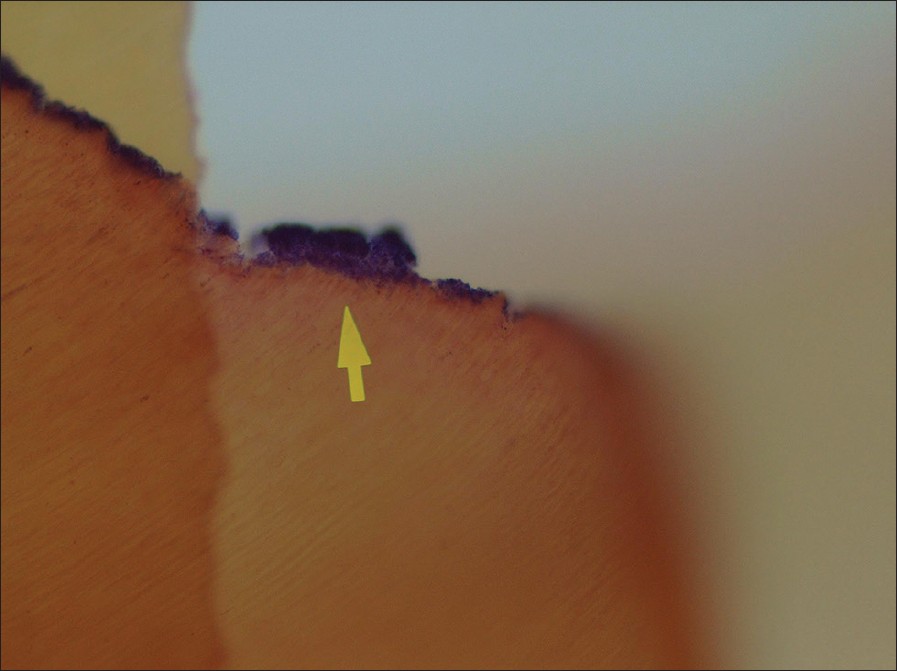

Bacterial microleakage of aged adhesive restorations |

Nevin Cobanoglu, Emine Kara, Nimet Unlu, Fusun Ozer DOI:10.4103/2278-9626.149669 Objective: The aim of this study was to investigate the marginal bacterial leakage of two self-etch adhesive systems after long-term water storage. Materials and Methods: Class V cavities were prepared on the buccal and lingual surfaces of extracted premolar teeth. After the sterilization of the teeth, four cavities were not restored for control purposes, whereas the other teeth were divided into two groups (n = 16 cavities each): Clearfil Protect Bond (CPB), Clearfil SE Bond (CSE). After the application of the bonding agent, cavities were restored with a composite resin. Then, the teeth were thermo cycled, stored in saline solution for 6 months and put into a broth culture of Streptococcus mutans. The teeth were fixed, sectioned and stained using the Gram-Colour modified method. The stained sections were then evaluated under a light microscope. The bacterial leakage was scored as: 0 - absence of stained bacteria, 1 - bacterial staining along the cavity walls, 2 - bacterial staining within the cut dentinal tubules. The data were analysed using the Kruskal-Wallis and Mann-Whitney U-test (P = 0.05). Results: The bacterial staining was detected within the cut dentinal tubules in all control cavities, in three cavities in the CSE group and one cavity in the CPB group. There were no observed statistically significant differences between the bacterial penetrations of the two bonding systems (P > 0.05). Conclusion: Both bonding systems provided acceptable prevention of marginal bacterial leakage after long-term water storage. |